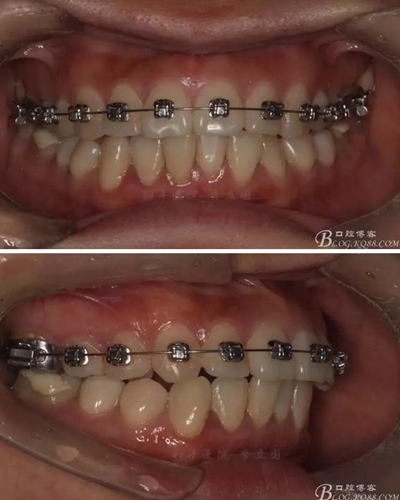

該病例主要為17、27頰側(cè)位同時伴有伸長,當(dāng)然種植支抗可以解決,但還有簡單實用的辦法嗎?如圖,在橫腭桿遠中延伸出牽引鉤,位置盡量遠離合平面,7粘舌側(cè)扣,牽引力的方向為壓低及舌向,下圖為兩個月的效果,17已到位,27還未到位。